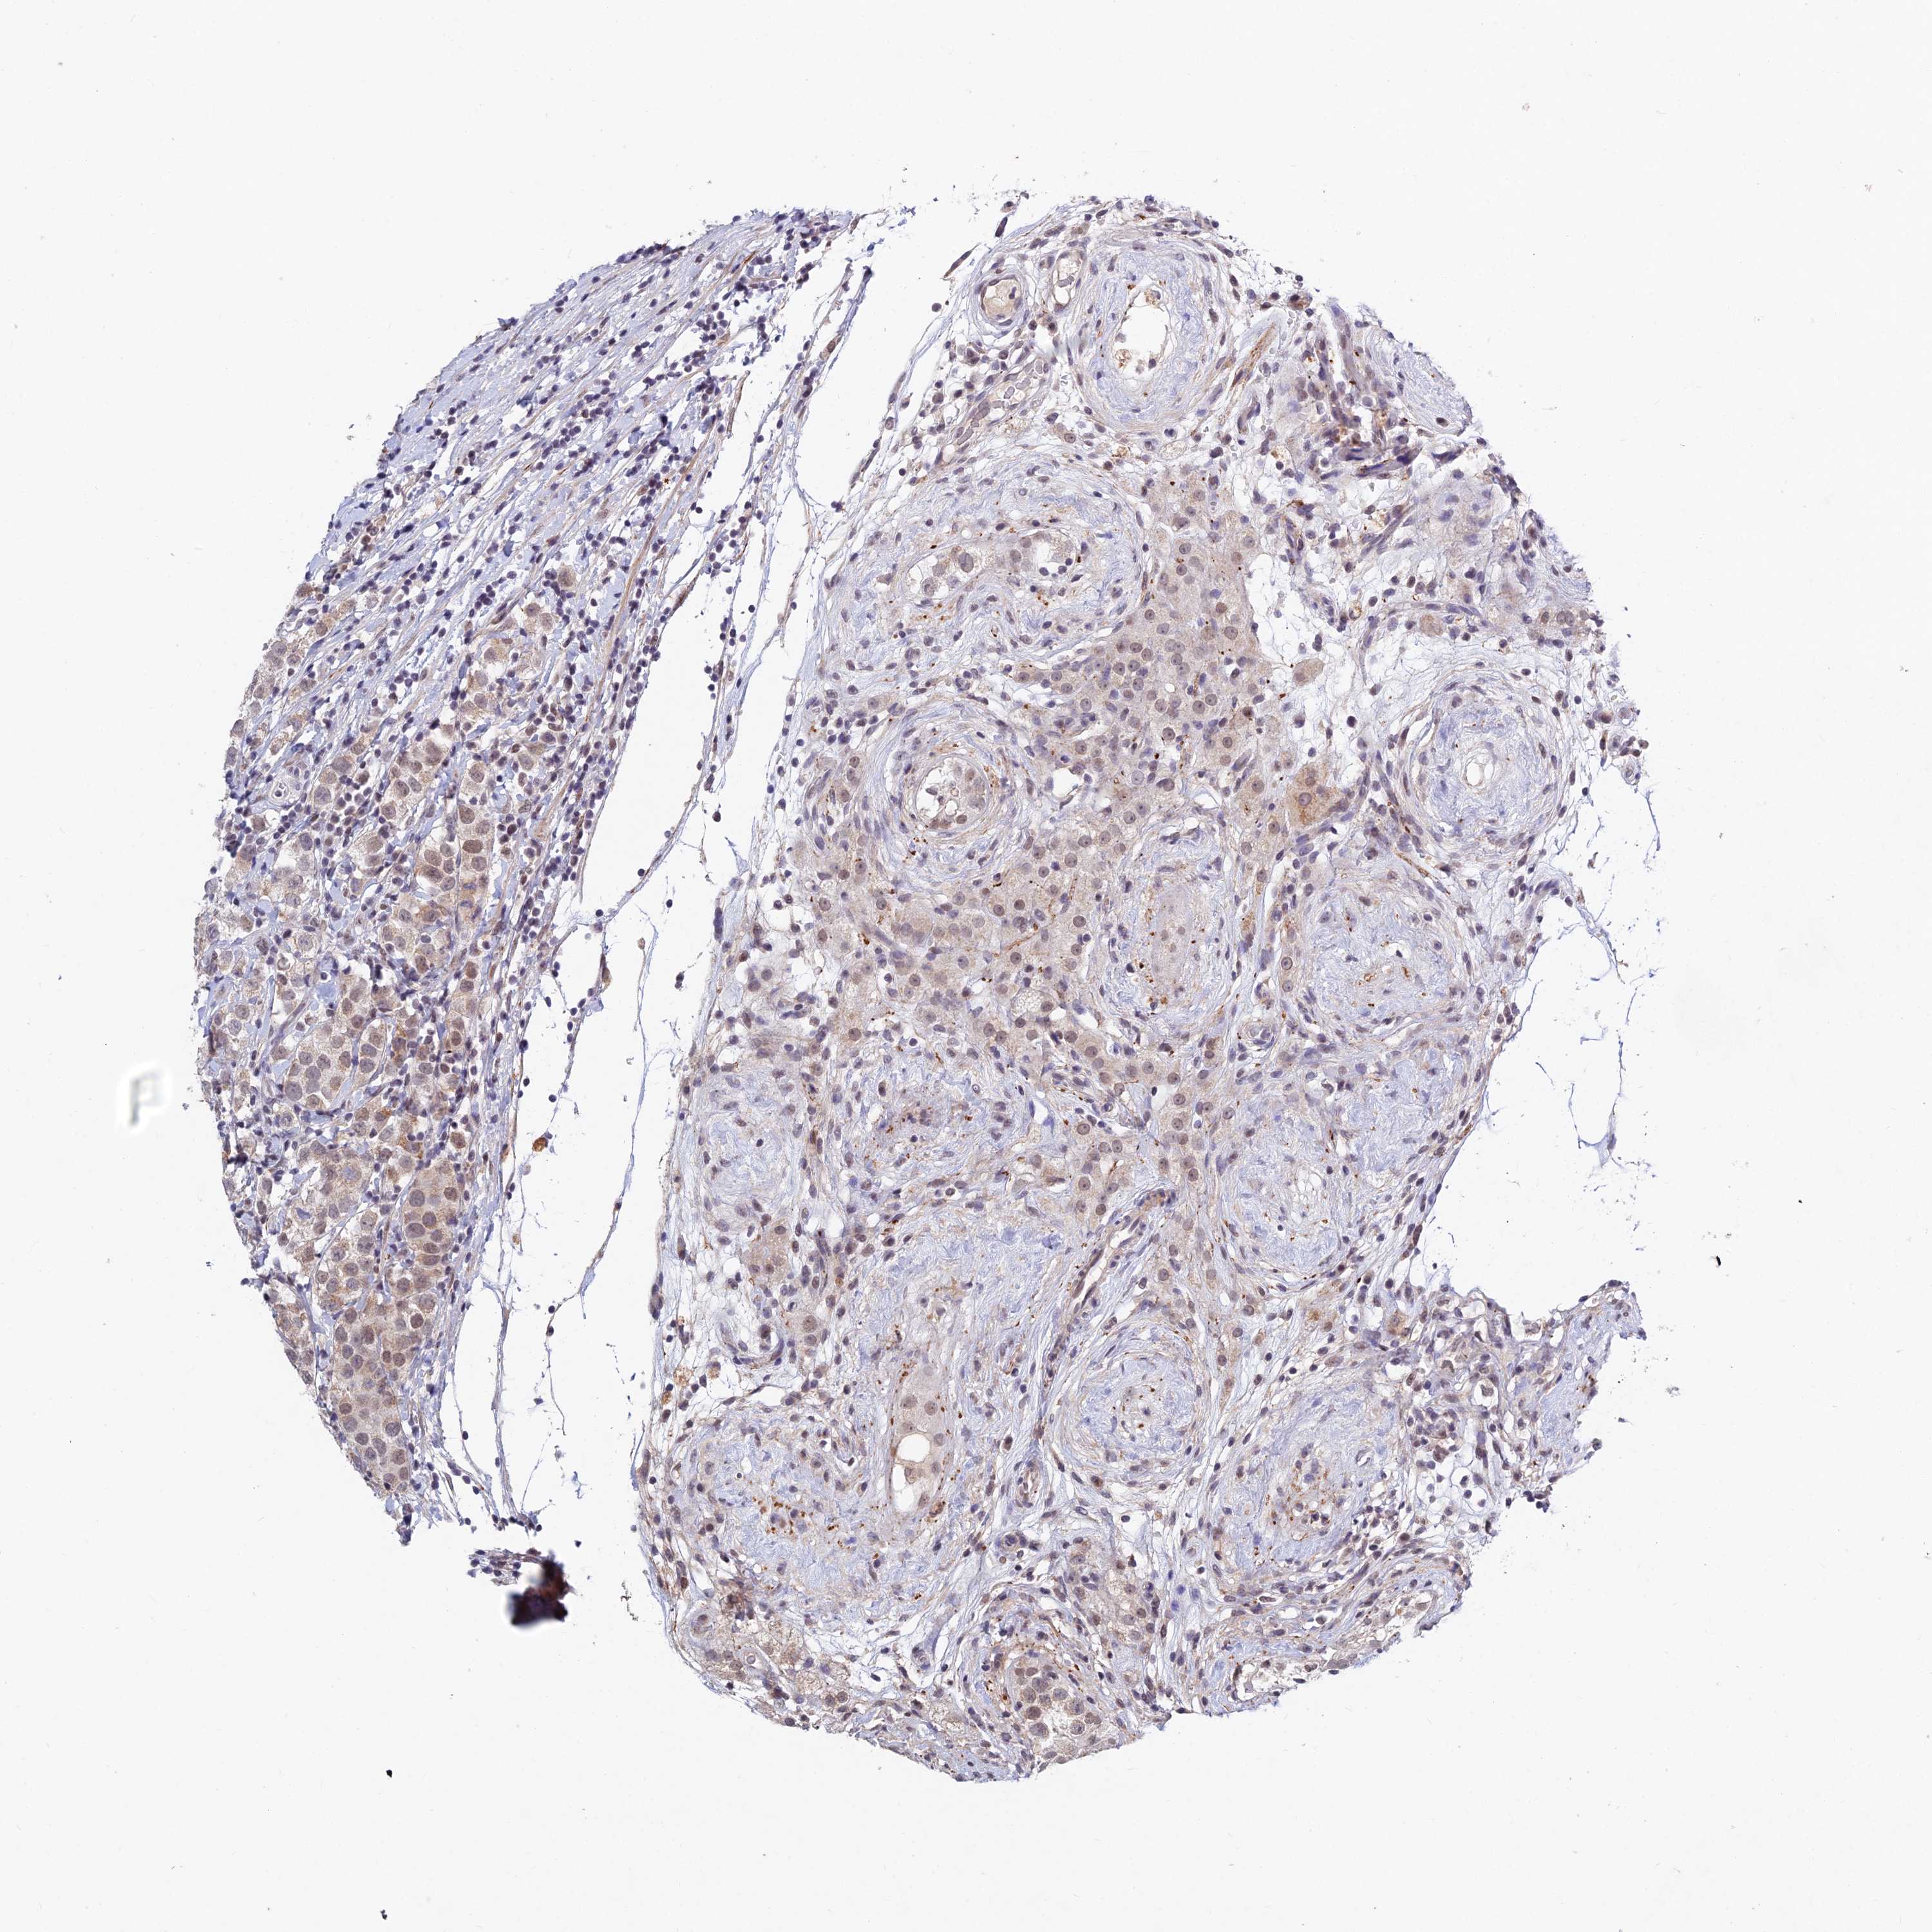

TESTIS CANCER - Protein expressioni

A mouse-over function shows sample information and annotation data. Click on an image to view it in a full screen mode. Samples can be filtered based on level of antibody staining by selecting one or several of the following categories: high, medium, low and not detected. The assay and annotation is described here.

Note that samples used for immunohistochemistry by the Human Protein Atlas do not correspond to samples in the TCGA dataset.

Antibody stainingi

Antibody staining in the annotated cell types in the current human tissue is reported as not detected, low, medium, or high, based on conventional immunohistochemistry profiling in selected tissues. This score is based on the combination of the staining intensity and fraction of stained cells.

Each image is clickable and will lead to virtual microscopy that enables deeper exploration of all samples and also displays staining intensity scores, fraction scores and subcellular localization as well as patient and tissue information for each sample.

Antibody HPA043575

Antibody HPA049457

Staining

High

Medium

Low

Not detected

Intensity

Strong

Moderate

Weak

Negative

Quantity

>75%

75%-25%

<25%

None

Location

Nuclear

Cytoplasmic/membranous

Cytoplasmic/membranous,nuclear

Carcinoma, Embryonal, NOS

Seminoma, NOS